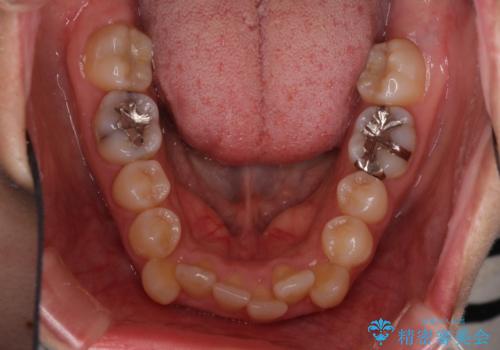

- 上下の八重歯を気にして来院された患者様です。

八重歯の後ろの歯を1歯抜歯し、補助装置(リンガルアーチ)を用いて八重歯の位置を改善し、その後インビザラインにより矯正治療を行うこととしました。

右側のみ上下小臼歯を抜歯したため、上下の正中が右にずれてしまう可能性があります。

また、元々右側は上下が咬み合っていないため、矯正をしても咬み合わないことも考えられました。

治療期間はかかりましたが、正中も合い、綺麗な仕上がりとなりました。